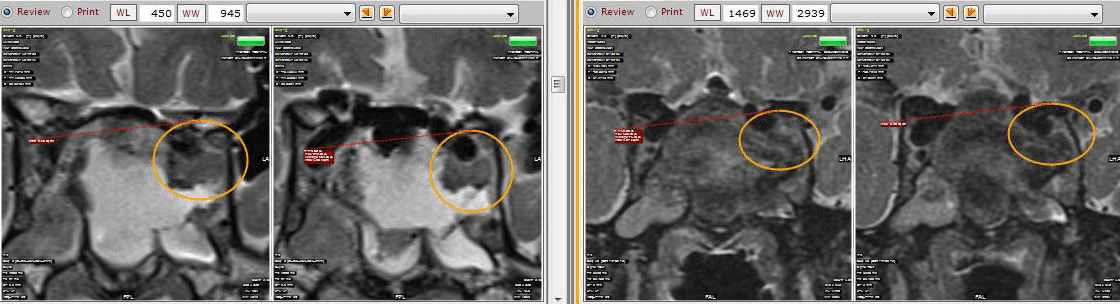

Case 2: 35/ M

- Pre-operative sagittal contrast enhanced T1W image shows a sellar mass with suprasellar extension (Figure 4)

- Intra-operative MRI (Figure 5) shows residual enhancing tumour, which was then taken up again for resection. Post operative MRI (Figure 6) shows a thin enhancing capsule with no residual tumour.

Figure 4

Figure 5

Figure 6